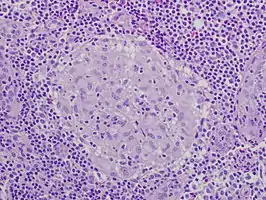

Granuloma without necrosis in a lymph node of a person with sarcoidosis

Granuloma without necrosis in a lymph node of a person with sarcoidosis Granuloma with central necrosis in a lung of a person with tuberculosis: Note the Langhans-type giant cells (with many nuclei arranged in a horseshoe-like pattern at the edge of the cell) around the periphery of the granuloma. Langhans-type giant cells are seen in many types of granulomas and are not specific for tuberculosis.